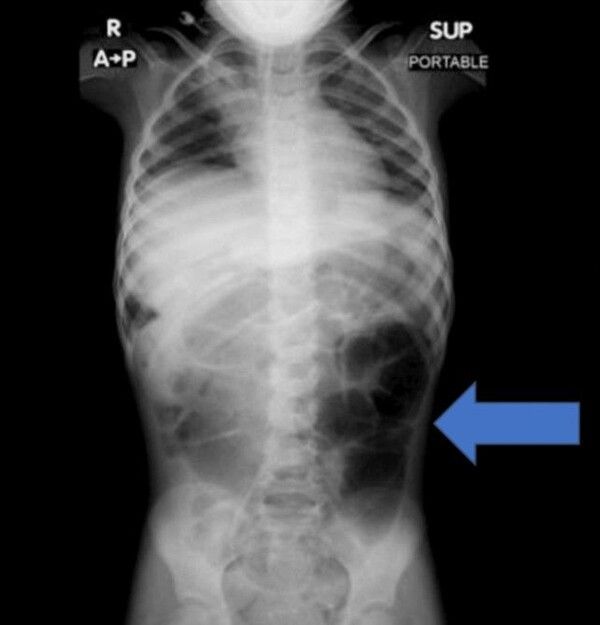

복통을 호소하던 6세 여아의 위장 안에서 예상치 못한 이물질이 발견된 사례가 학술지에 보고됐다.

뉴시스 보도에 따르면, 20일 의학 저널 '큐레우스(Cureus)' 실린 보고에 따르면, 사우디아라비아에 거주하는 6세 여자아이는 수주간 이어진 복통과 소화 장애 증상으로 병원을 찾았다. 정밀 검사를 진행한 결과, 의료진은 위 내부에 비정상적으로 큰 이물질이 자리 잡 것을 확인했다.

수술을 통해 제거된 물질의 정체는 다량의 머리카락이 엉켜 형성된 덩어리였다. 해당 덩어리는 위에 머무는 데 그치지 않고 소장 일부까지 길게 이어진 상태였던 것으로 전해졌다.

의료진은 보고서를 통해 "소아 환자에게 반복적인 복통이나 구토, 식욕 저하 증상이 장기간 지속될 경우 위장관 내 이물질 가능성을 염두에 둬야 한다"며 "영상 검사를 통한 조기 진단과 신속한 치료가 중요하다"고 강조했다.

라푼젤 증후군은 머리카락을 반복적으로 뽑는 행동과 이를 삼키는 습관이 함께 나타나면서, 섭취된 모발이 위장 안에 쌓여 덩어리를 이루는 매우 드문 질환이다.

이 병명은 독일 그림 형제가 소개한 동화 '라푼젤'에서 따왔다. 동화 속 주인공이 높은 탑에서 길게 늘어뜨린 머리카락으로 외부와 이어지는 장면처럼, 실제 질환에서도 머리카락으로 형성된 이물질이 위에서 시작해 실타래처럼 장까지 길게 이어지는 양상을 보이기 때문이다.